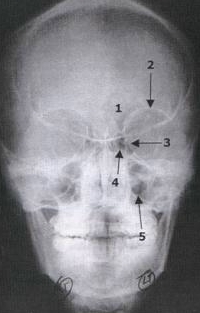

Caldwell View

Evaluation The Upper And Middle Thirds Of The Face